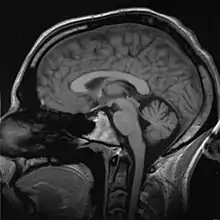

C'est dans la seconde moitié du XXe siècle que se situe une grande révolution dans l'étude du cortex cérébral, avec la mise au point de méthodes d'imagerie cérébrale non invasives. Le médecin peut voir le cerveau fonctionner sans ouvrir le crâne. Jusque-là, les radiographies standards ne donnaient que des images inexploitables (le cerveau n'étant pas radio-opaque) et l'angiographie cérébrale ne permettait de voir que les axes vasculaires cérébraux. « Grâce à l’introduction des techniques de neuroimagerie, le niveau molaire de description a pu se substituer au niveau moléculaire dominant[5]. »

Ce fut d'abord le scanner qui permit de visualiser, pour la première fois le cerveau et les zones corticales avec une précision remarquable, puis la résonance magnétique nucléaire (IRM) a considérablement modifié, à son tour, l'étude iconographique des structures corticales.

En 1938, le principe de résonance magnétique nucléaire est découvert par Isidor Isaac Rabi. Cette découverte aboutira, en 1973, à la mise au point de ce qui allait devenir l'imagerie par résonance magnétique ou IRM, simultanément par Paul Lauterbur et Peter Mansfield qui reçurent conjointement un prix Nobel (Prix Nobel de physiologie ou médecine) en 2003.